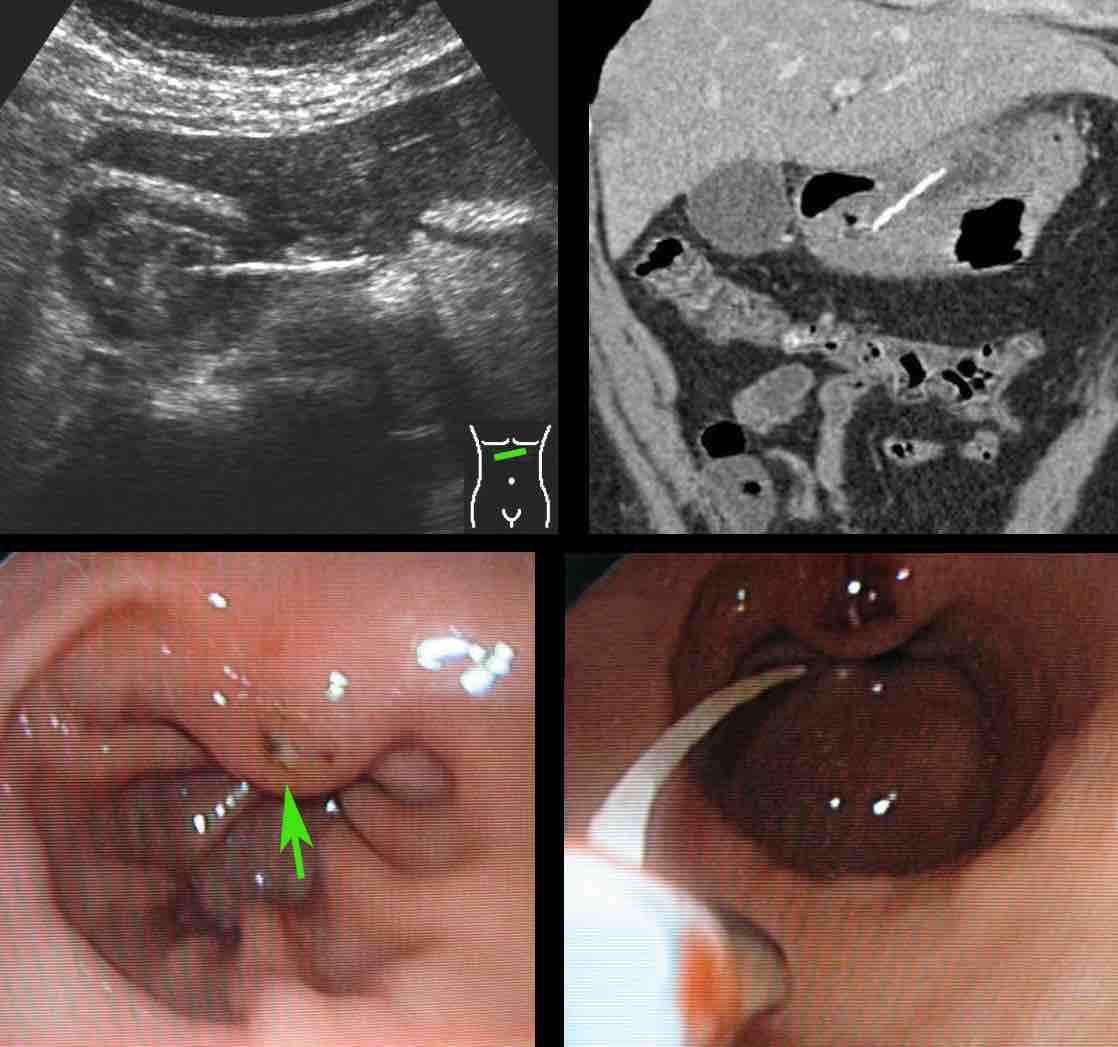

Bệnh nhân nữ 59 tuổi với cơn đau thượng vị không điển hình kéo dài hai ngày.

Siêu âm phát hiện dày thành đáng kể vùng hang vị trước môn vị, trong đó có cấu trúc tăng âm, dạng cong (đầu mũi tên), nghi ngờ xương cá.

CT xác nhận chẩn đoán.

Lưu ý rằng xương cá (mũi tên) có thể dễ dàng bị bỏ sót nếu chỉ xem trên mặt phẳng cắt coronal của CT.

Bệnh nhân hồi phục tốt sau khi lấy dị vật qua nội soi.

Siêu âm và CT cho thấy xương cá xuyên thủng thành dạ dày ngay trước môn vị.

Khi nội soi dạ dày không tìm thấy xương cá, mà chỉ thấy phù nề niêm mạc cục bộ với loét trung tâm (mũi tên).

Việc đưa sâu dụng cụ kẹp lớn vào vùng này cuối cùng đã thành công trong việc gắp được xương cá.